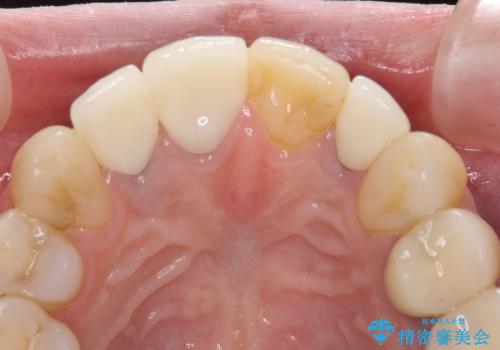

3歯別々に治療したクラウンは、どれも未治療の前歯を異なる色調で、口元が縞模様の印象でした。

更に、土台やフレームの金属色により、歯肉ラインが黒ずんでしまっていました。

必要な歯には根管治療を行い、金属を使わない土台を植立した上で、オールセラミッククラウンにて補綴することとしました。